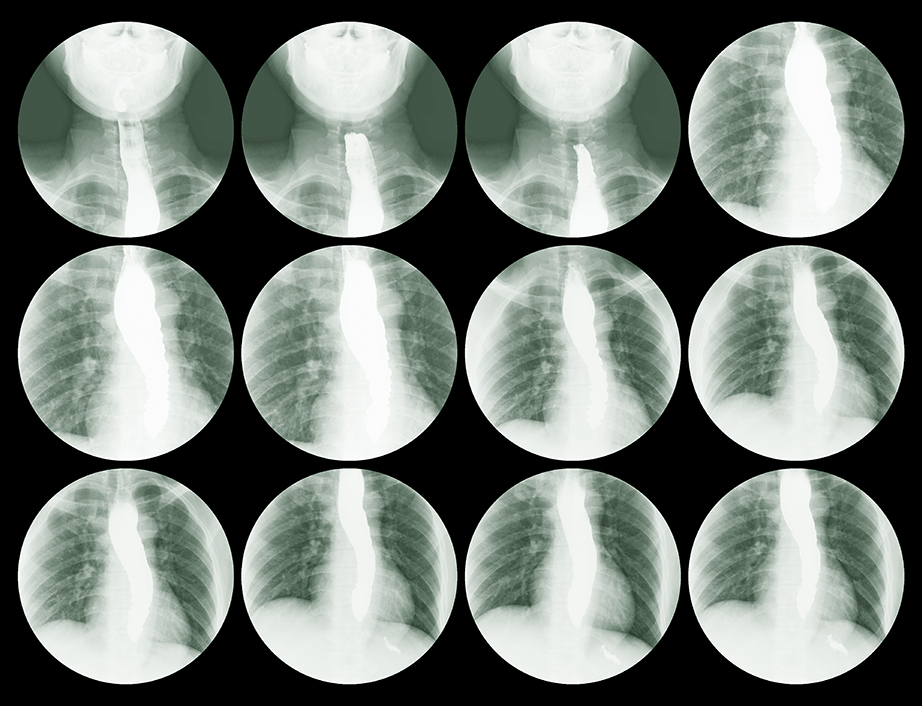

• Esofagograma